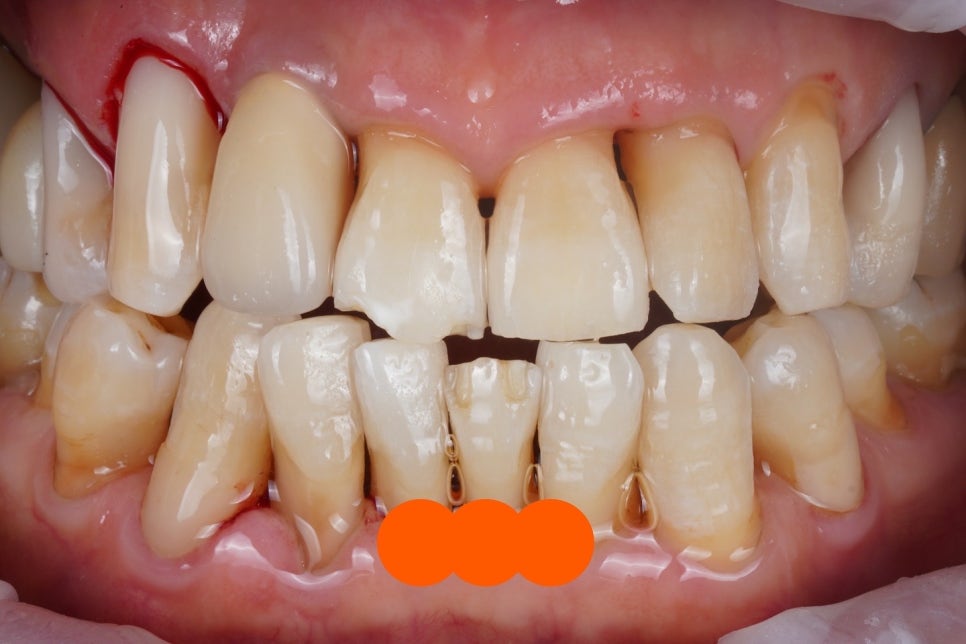

착색물질을 스위스 에어플로우 GBT

'파우더 스케일링'을 통해

깨끗하게 지워드렸고,

변색되고 떨어진 치경부 레진도

모두 교체해드렸습니다.

그냥 봐도 전후 차이가 굉장하죠?

파우더 스케일링을 하면 이렇게

치아 색이 한톤 밝아지는 효과도 있더라고요

특히 뿌리가 드러난 경우에는 몇단계 이상

밝아지는 것 같습니다.